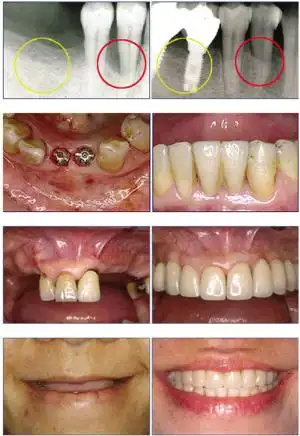

种植牙前后对比图.